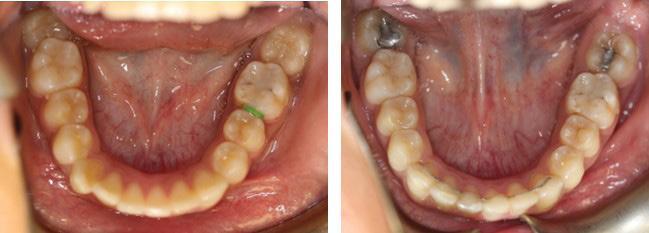

A healthy 12-year-7-month-old female, with an adult dentition, presented with a chief complaint of “teeth not coming in straight,” as was identified to her and her parents by a referring dentist. On clinical examination, the patient had pleasing facial esthetics on an orthognathic skeletal base. Intraorally, the patient had Angle Class I molar relationship bilaterally with well-aligned arches but impacted mandibular second molars with partially visible crowns (Figure 1). The panoramic radiograph confirmed the mesioangular impactions of the mandibular second molars bilaterally along with the third molars at the early crown calcification stage of development (Figure 1). An increase in inclination of second molars can be seen bilaterally, on examination of panoramic radiographs at ages of 10 years and 5 months and 11 years 10 months, which were 17 months apart (Figures 1 and 2).

Given the clinical and radiographic presentations, the treatment plan to surgically extract the developing third molars prior to orthodontic treatment was presented to the patient and parents for their consent. The mandibular third molars were surgically removed by an oral surgeon under deep sedation. A follow-up panoramic radiograph obtained approximately 7 months following the surgery, at 12 years and 7 months of age, revealed completely healed third molar extraction sites, spontaneous improvement in the angulation of the left mandibular second molar but little change in the angulation of the right second molar. Orthodontic records were obtained at this stage and treatment was initiated with complete maxillary and mandibular orthodontic MBT, 0.022’’ slot size brackets. Orthodontic bands were placed on the mandibular first permanent molars that were modified with laboratory soldered Halterman appliances from the lingual surfaces of the bands. Orthodontic buttons were bonded on the occlusal surfaces of the impacted molars. Initial disimpaction of the second molars was achieved by sequential distal traction with the use of chain elastics. When the molars were sufficiently uprighted and the buccal surfaces were visible, orthodontic direct-bond brackets were placed and the Halterman arm and occlusal buttons were removed. All further orthodontic tooth movements including uprighting of the second molars were achieved through 4-6-weekly sequential changes of Nickel-Titanium followed by stainless steel archwires. The sequence of archwires were as follows: Ni-Ti0.012”, 0.014”, 0.016”, 0.018” 0.016x0.022”, 0.017x0.025 and SS- 0.016x0.022”, 0.017x0.025, all wires ligated with elastics. Bonded lingual wire retainers, as well as removable Essix retainers, were delivered to the patient to maintain the results.

The left photo shows the impacted second molars, post third molar extraction surgery but pre-orthodontic treatment. The photograph on the right shows 5-year follow-up post-orthodontic treatment. Note mesio-occlusal caries restored with amalgam restorations during the course of orthodontic treatment.

Fig. 1: Initial presentation of mesioangular impacted mandibular second molars at 10 years and 5 months of age. Note that the mandibular third molars are at about a third crown completion stage of development.only for the understanding purpose.

Fig. 5a: Age: 12 years, 7 months

Fig. 5b: Age: 17 years 7 months